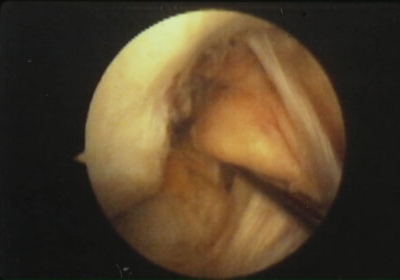

ARTROSCOPIAS

Esta técnica quirúrgica mínimamente invasiva nos permite mediante abordajes percutáneos diagnosticar y operar en la rodilla y otras articulaciones, con un ingreso ambulatorio y una rápida recuperación.¿Qué podemos tratar?

Mediante esta técnica podemos tratar lesiones meniscales (meniscectomia) o sutura del menisco; en casos muy selectivos puede indicarse un trasplante de menisco. También se pueden tratar condropatías, inestabilidades femoropatelares, osteocondritis, lesiones focales del cartílago y patología de la sinovial. Tambien lesiones ligamentosas como la del Ligamento cruzado anterior (LCA), el más intervenido en el ámbito del deporte.¿Cómo reconstruir el LCA?

Las técnicas de reconstrucción del LCA son variadas pero siempre utilizando un tendón del propio paciente o del banco de tejidos (normalmente el tendón rotuliano o los tendones isquiotibiales) para implantar en la rodilla afectada vía técnica artroscópica. Consiguiendo un éxito en el 90 % de los casos y con una reincorporación al deporte del lesionado entre 4 y 6 meses.